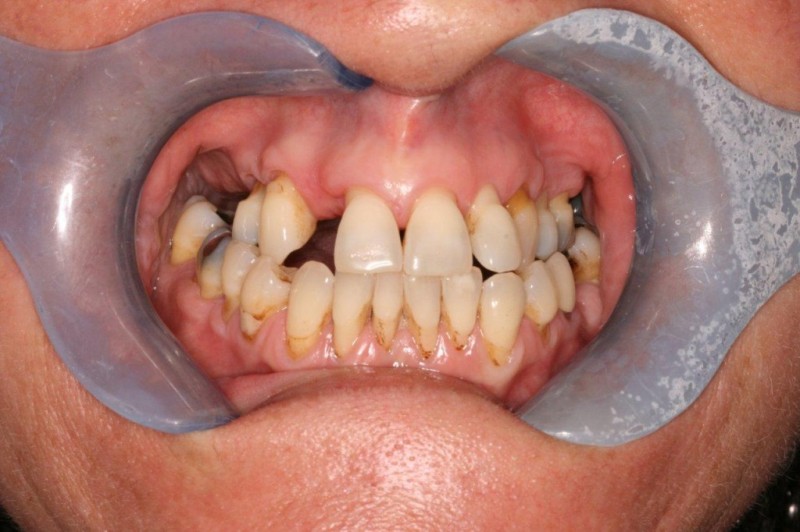

Inflammation of the gums is initially called gingivitis. People who are susceptible to gum disease may progress to get periodontal disease.

Over time, Periodontal disease can damage your ability to bite and lead to tooth loss.

To make sure this doesn't happen, we start treatment promptly to stop the process and maintain your long-term dental health.

Our Periodontal treatments include:

• Full mouth charting